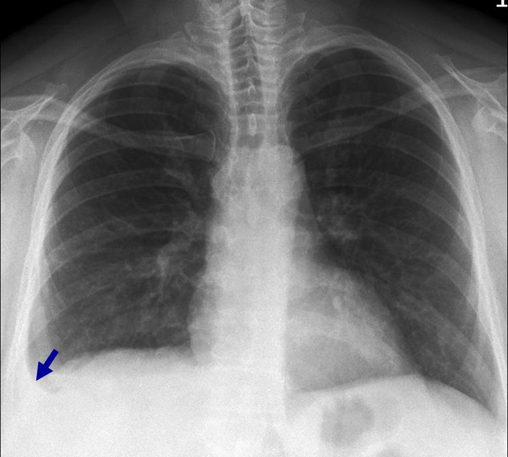

What is this x-ray showing?

What 3 findings suggest this?

Right Tension Pneumothorax w/

Left Tension Pneumothorax

Flattening of left diaphragm

Deviated to the right

Left pneumothorax